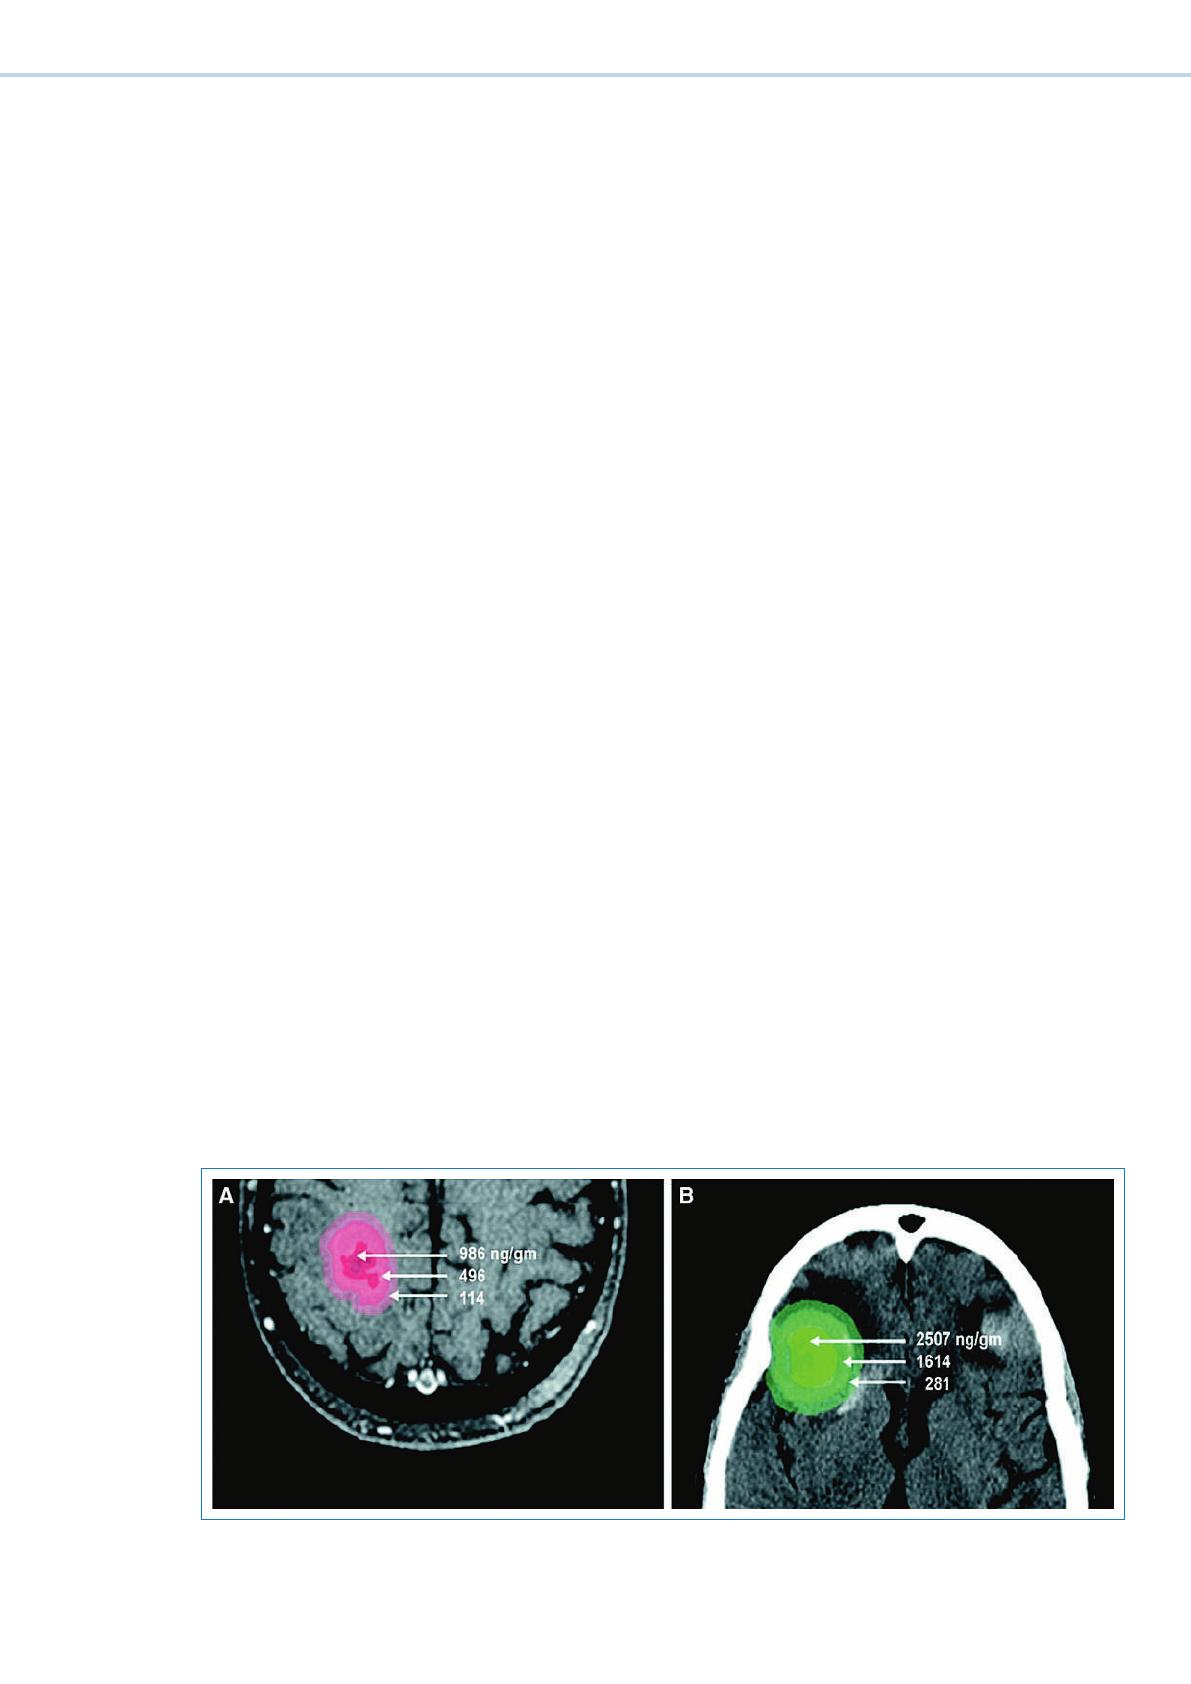

Une barrière hémato-encéphalique (BHE) intacte est im-

perméable à la plupart des cytostatiques. Une prise du

produit de contraste de la lésion tumorale suggère ce-

pendant l’existence d’une perméabilité au moins partielle

de la BHE, ce qui a aussi été observé pour les substances

chimiothérapeutiques (g. 3 x) [5]. En outre, la plu-

part des vaisseaux des métastases ont les caracté-

ristiques de la tumeur primaire. Le taux de réponse

des métastases cérébrales à un traitement systémique

est comparable à celui des métastases extra-crâniennes.